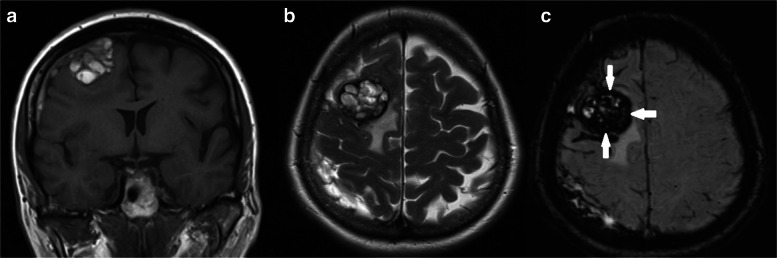

A 63-year-old woman admitted in our clinic with complaints of intensive headaches in right frontal region and right orbit lasting for 1 month before. There was no history of vomiting, nausea, convulsions or unconsciousness, head trauma or early episodes of headaches. Physical and neurological examination was unremarkable. Magnetic resonance imaging showed a right chronic subdural hematoma with a slight midline brain shift and a tumor mass with a “dura-tail” and “popcorn signs” and hemosiderin deposits in the right frontal region (Fig. 1). Considering the cavernoma resection of this lesion was planned.

Fig. 1.

a Preoperative MRI. T1 weighted image, coronal plane. A mass sized 32 * 30 * 35 mm on the surface of the right frontal lobe, with heterogeneous iso- hyperintensive signal (lesion has «popcorn» sign), right chronic subdural hematoma with midline brainshift 3 mm. b Preoperative MRI. T2 weighted image, axial plane. This mass shows similar popcorn-shaped characteristics with perifocal edema. c Preoperative MRI. SWI sequence, axial plane. Ring of hypointensity around lesion (arrows)